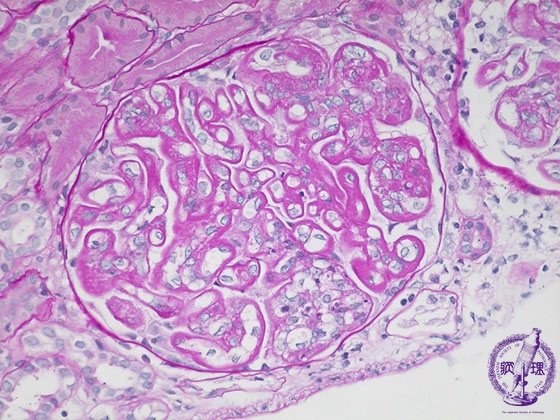

- 12.Kidney and Urinary System

- (6)Lupus Glomerulonephritis

Microscopic findings ( PAS, high power view): The basement membrane is markedly thickened and has a wire-loop appearance (yellow arrows). An endocapillary cellular proliferation containing neutrophil aggregates is focally observed (yellow dotted line).